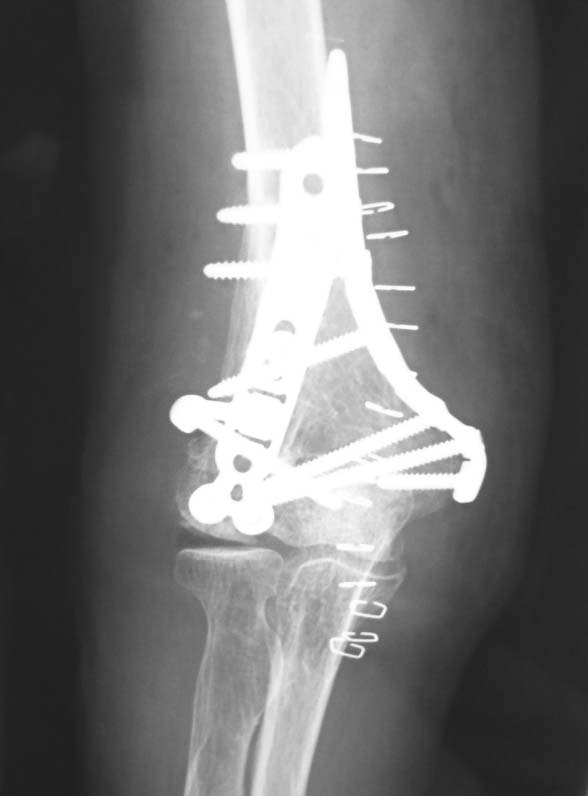

単純X線像では、骨折部にやや不整な像を認めます。内固定材料はロッキングプレートですが、このような症例では注意が必要だと感じています。

案の定、CTでは外側に骨癒合不全を認めます。前方皮質は骨癒合しているようですが、その部分より後方は内側しか骨癒合していません。

このような症例で安易に抜釘すると、術後に病的骨折を併発するリスクが高まります。この症例に限らず、ロッキングプレート使用例ではこのようなことが多い印象を受けます。

比較的大きな外力の加わった骨折症例に対してロッキングプレートで内固定されている症例では、抜釘する際に CTを施行して骨癒合しているか確認することをお勧めします。